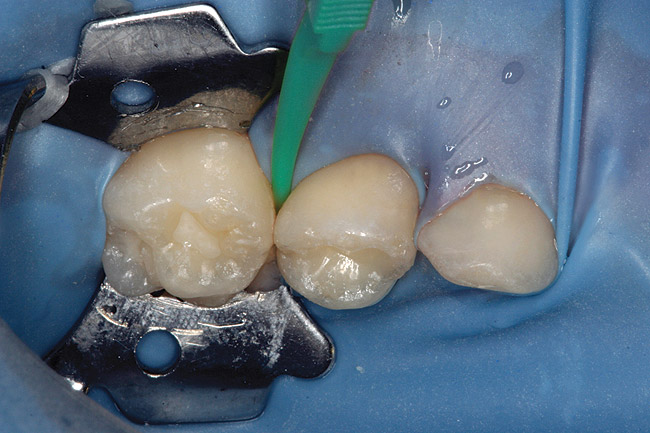

Figure 12  Final view showing treated surface of mesial of tooth A.

Figure 12

Specially designed dental wedges are inserted to slightly separate the carious tooth from adjacent teeth. A 15% hydrochloric gel is used to remove the "pseudointact" surface and open the pore system of the incipient lesion body (Figure 7).85 After rinsing (Figure 8), the area is dried with ethanol (Figure 9), followed by dry air. Then, the infiltrant is applied and allowed to penetrate the lesion pores by capillary action for 3 minutes (Figure 10). Any excess material is removed with dental floss, and the infiltrant is light cured from three angles for 40 seconds (Figure 11). A second layer of infiltrant is applied for 1 minute, and light cured for 40 seconds (Figure 12).86 It should be noted that the infiltrant is not radiopaque because fillers would affect the viscosity. Efficacy of the treatment can be tracked at future visits by lack of lesion progression.